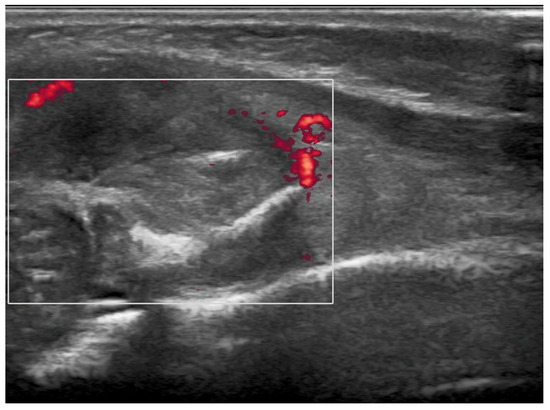

Brain ultrasound performed after birth was normal. Blood tests were negative for infectious diseases. Complete blood count, calcium, glycemia, lipid profile, and urine test were normal, and tumor markers were negative. The first diagnostic hypothesis was shaft fracture of the right humerus, but X-ray of the right arm and forearm was negative. Ultrasonography showed a solid, slightly vascularized lesion with a hyperechoic center and a surrounding ring, involving brachial muscle, compatible with intramuscular hematoma, which caused compression of the radial nerve (Figure 1). Studies on nerve conduction revealed that radial motor compound muscle action potential (CMAP) and radial sensory nerve action potential (SNAP) had significantly reduced amplitude distal to the elbow. A watchful, waiting attitude with physiotherapy was performed. The newborn had benefited from passive movement-type physiotherapy sessions and sensorimotor facilitation for upper limb integration. The patient was also fitted with a custom-designed static splint made of thermo-moldable plastic that had perforations, immobilizing only his right wrist and fingers in a neutral position (Figure 2). Thankfully, there were no signs of contractures or stiffness in the wrist or any of the finger joints. At 2 months of life, a second X-ray showed proximal radius deformity, due to a solid mass compression (Figure 3A,B). Magnetic resonance imaging of the right upper limb revealed a solid, hypovascular mass with an area of necrosis infiltrating and involving the radial head, and fatty atrophy in line with proximal extensor muscle denervation alterations. The mass was mildly hypointense on T1-weighted sequences and hyperintense on T2-weighted images, with mostly peripheral post-contrast enhancement (Figure 4A,B). Total body MRI scan made it possible to evaluate the presence of similar lesions in other parts of the body, so to exclude diagnosis of infantile myofibromatosis. CT angiography of the right upper limb was performed to evaluate upper extremity arterial abnormalities and it showed regular patency of arterial vessels, with dislocation of the brachial artery by the mass. The main differential diagnosis included fibrous hamartoma of infancy, juvenile hyaline fibromatosis, infantile fibrosarcoma, or Ewing sarcoma/primitive neuroectodermal tumor. A fine needle biopsy of the lesion confirmed that it was a benign mesenchymal tumor compatible with myofibroma. Genetic testing revealed no familial inheritance. Following physiotherapy, with the same activity improving with taping for the wrist and fingers’ extension, then replaced by a Lycra dynamic orthosis (flexa) (Figure 5) during 3–4 h when awake and stretching exercises, an improvement in the infant’s right arm motility was seen within 4–5 months of birth, but no activation of the wrist and finger extensors was observed. Therefore, it was advised to explore the radial nerve surgically in case of compressive neuropathy.

Figure 1.

Preoperative ultrasound imaging of right elbow: soft tissue lesion on the anterolateral surface of the right forearm characterized by a nonhomogeneous echotexture and hyperechogenic spots and thin hyperechogenic lamella in its context. Intralesional vascularization is minimal. The surface of the cortex of the proximal radial metaphysis facing the mass is irregular. There is no evidence of chondro-epiphyseal detachment.